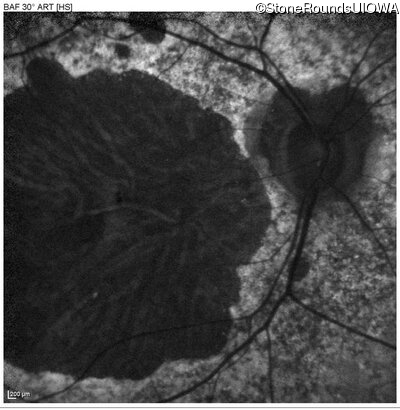

Blue Autofluorescence - Right - 10/200 -2 sc

Exemplar

Blue Autofluorescence - Left - 10/200 -3 sc